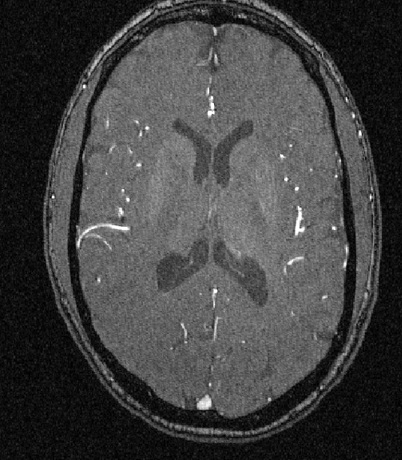

Arteries branch out mostly as a tree from the heart and deliver blood to the entire body. In particular arteries transport oxygen and nutrient-rich blood to the brain. Magnetic Resonance Angiography (MRA) is a technique in medical imaging to visualize arteries. MRA uses the fact that blood flowing in the arteries has a distinct magnetic signature. Full 3D image acquisition is achieved by combining cross sectional 2D images. See Figures 1.4 and 1.5 below for an MRA slice and an artery reconstruction for the same subject. A limiting factor is that MRA has a resolution threshold and consequently there are arteries that are too small for detection. MRA detects only arteries which feed blood rich with oxygen and nutrients to the body, and not veins which carry depleted blood back to the heart.

The arteries visible in MRA are generally naturally described as a tree. In most regions of the body and at the level of resolution possible, arteries branch like a tree without any loops. A major part of this research has been opening up the possibility of using the space of phylogenetic trees as a mathematical basis for developing statistical methods for the study of artery trees. Phylogenetic trees have a common leaf set. However artery trees do not. A common leaf set is artificially introduced by determining points on the cortical surface that correspond across different people. The next section describes the details of representing brain artery systems as points in BHV treespace.